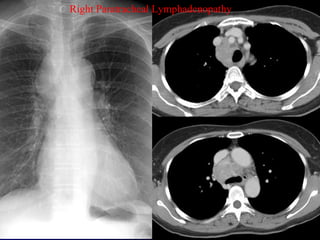

Rt. Paratracheal

Lymphadenopathy

(Lymphoma)

After Therapy

Where is the Lymphadenopathy?